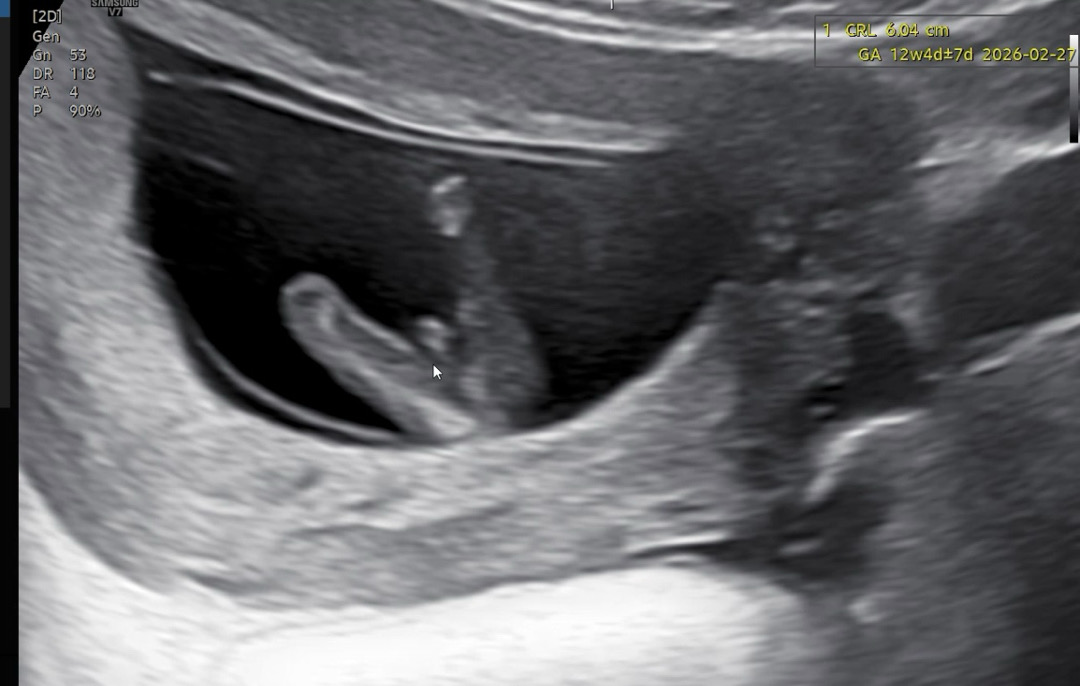

11주 6일 성별 확정일까요?

11주6일입니당 이정도면 성별 반전 없겠..죠..?

아유 귀여워요ㅋㅋ아들맘 축하드려요ㅋㅋ

오와 11주에도 저렇게 뚜렷할수가 있나봐요?? 저도 빨리 알고파요...🥹

그쵸.. 너무 뚜렷해서 아쉬운 1인입니당,, ㅋㅋㅋㅋ